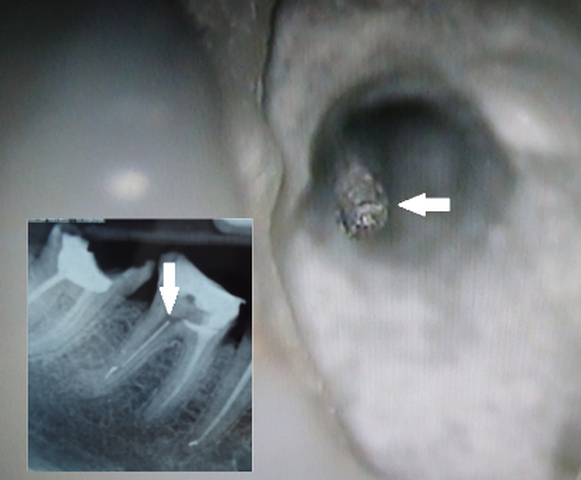

- lokalizowanie i usuwanie złamanych narzędzi oraz innych ciał obcych z kanału korzeniowego (ryc. 3 i 4).

Ryc. 3. Złamane narzędzie tkwiące w obrębie części koronowej kanału. Strzałka wskazuje widoczny w ujściu koronowy koniec złamanego fragmentu.

Ryc. 4. Fragment narzędzia tkwiący w kanale policzkowym zęba przedtrzonowego szczęki. Strzałka wskazuje kornowy koniec złamanego fragmentu.